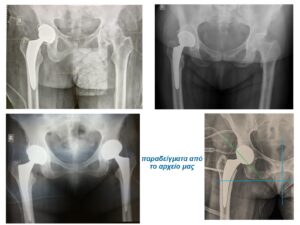

Στην εικόνα 6 απεικονίζεται η ακτινογραφία ασθενούς, από το αρχείο μας, με προχωρημένη αρθρίτιτδα και των δύο ισχίων. (Ο ασθενής υποβλήθηκε την ίδια μέρα σε ταυτόχρονη αρθροπλαστική AMIS και στα δύο ισχία του)

Στην εικόνα  8 παρουσιάζουμε ενδεικτικά τομές αρθροπλαστικής AMIS από προσωπικό αρχείο. Στην εικόνα 9 απεικονίζεται συγκριτικά η τομή AMIS bikini. Στην εικόνα 10 βλέπουμε το σχεδιασμό της τομής βάσει οδηγών σημείων, μετά την τοποθέτηση του ασθενούς στο ειδικό χειρουργικό τραπέζι AMIS.

Στην εικόνα 6 βλέπουμε την προεγχειρητική ακτινογραφία άνδρα 56 ετών που υποβλήθηκε σε ταυτόχρονη αρθροπλαστική AMIS με navigation robotic assistance. Στην εικόνα 21 ο προεγχειρητικός τρισδιάστατος σχεδιασμός, αναλυτικά. Στην εικόνα 22 η πλοήγηση από το σύστημα διεγχειρητικά, με απόλυτη ακρίβεια και το άριστο τελικό ακτινολογικό αποτέλεσμα. Ο ίδιος ασθενής στην επανεξέταση, 24 μέρες μετά την επέμβαση στο ιατρείο.